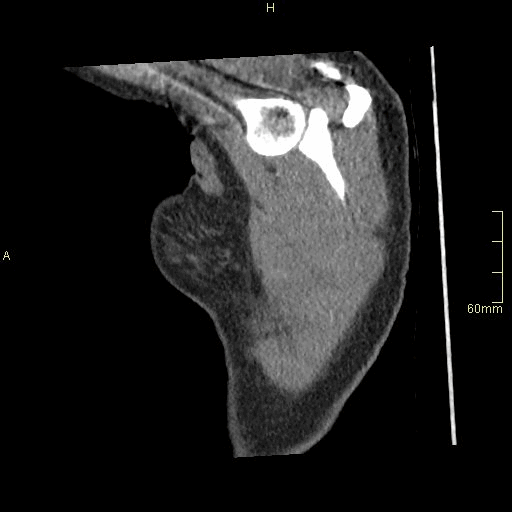

CTPA (Sagittal)

Portal Venous Abdomen (Sagittal)